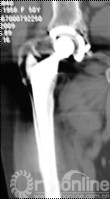

4例因发现腹股沟、或髂窝处渐大、隐痛不适包块而就诊;1例因大腿上外侧出现渐增大无痛性包块就诊;2例术后定期随访拍片发现假体周围局灶性骨溶解,进一步行三维CT扫面发现骨盆内炎性假瘤。所有患者X线片拍片均发现假体周围局灶性骨溶解,假体稳定固定。7例X线发现髋臼DeLee和Charnley II区骨溶解,1例同时伴有股骨侧外侧骨溶解(Gruen II区)。7例三维CT扫描均提示骨溶解区,其中6例CT提示骨盆内软组织包块,1例CT显示大腿前外侧软组织包快(图1)。

图1  CT片示股骨上段GruenII区骨溶解,外侧炎性假瘤形成(箭头所示)